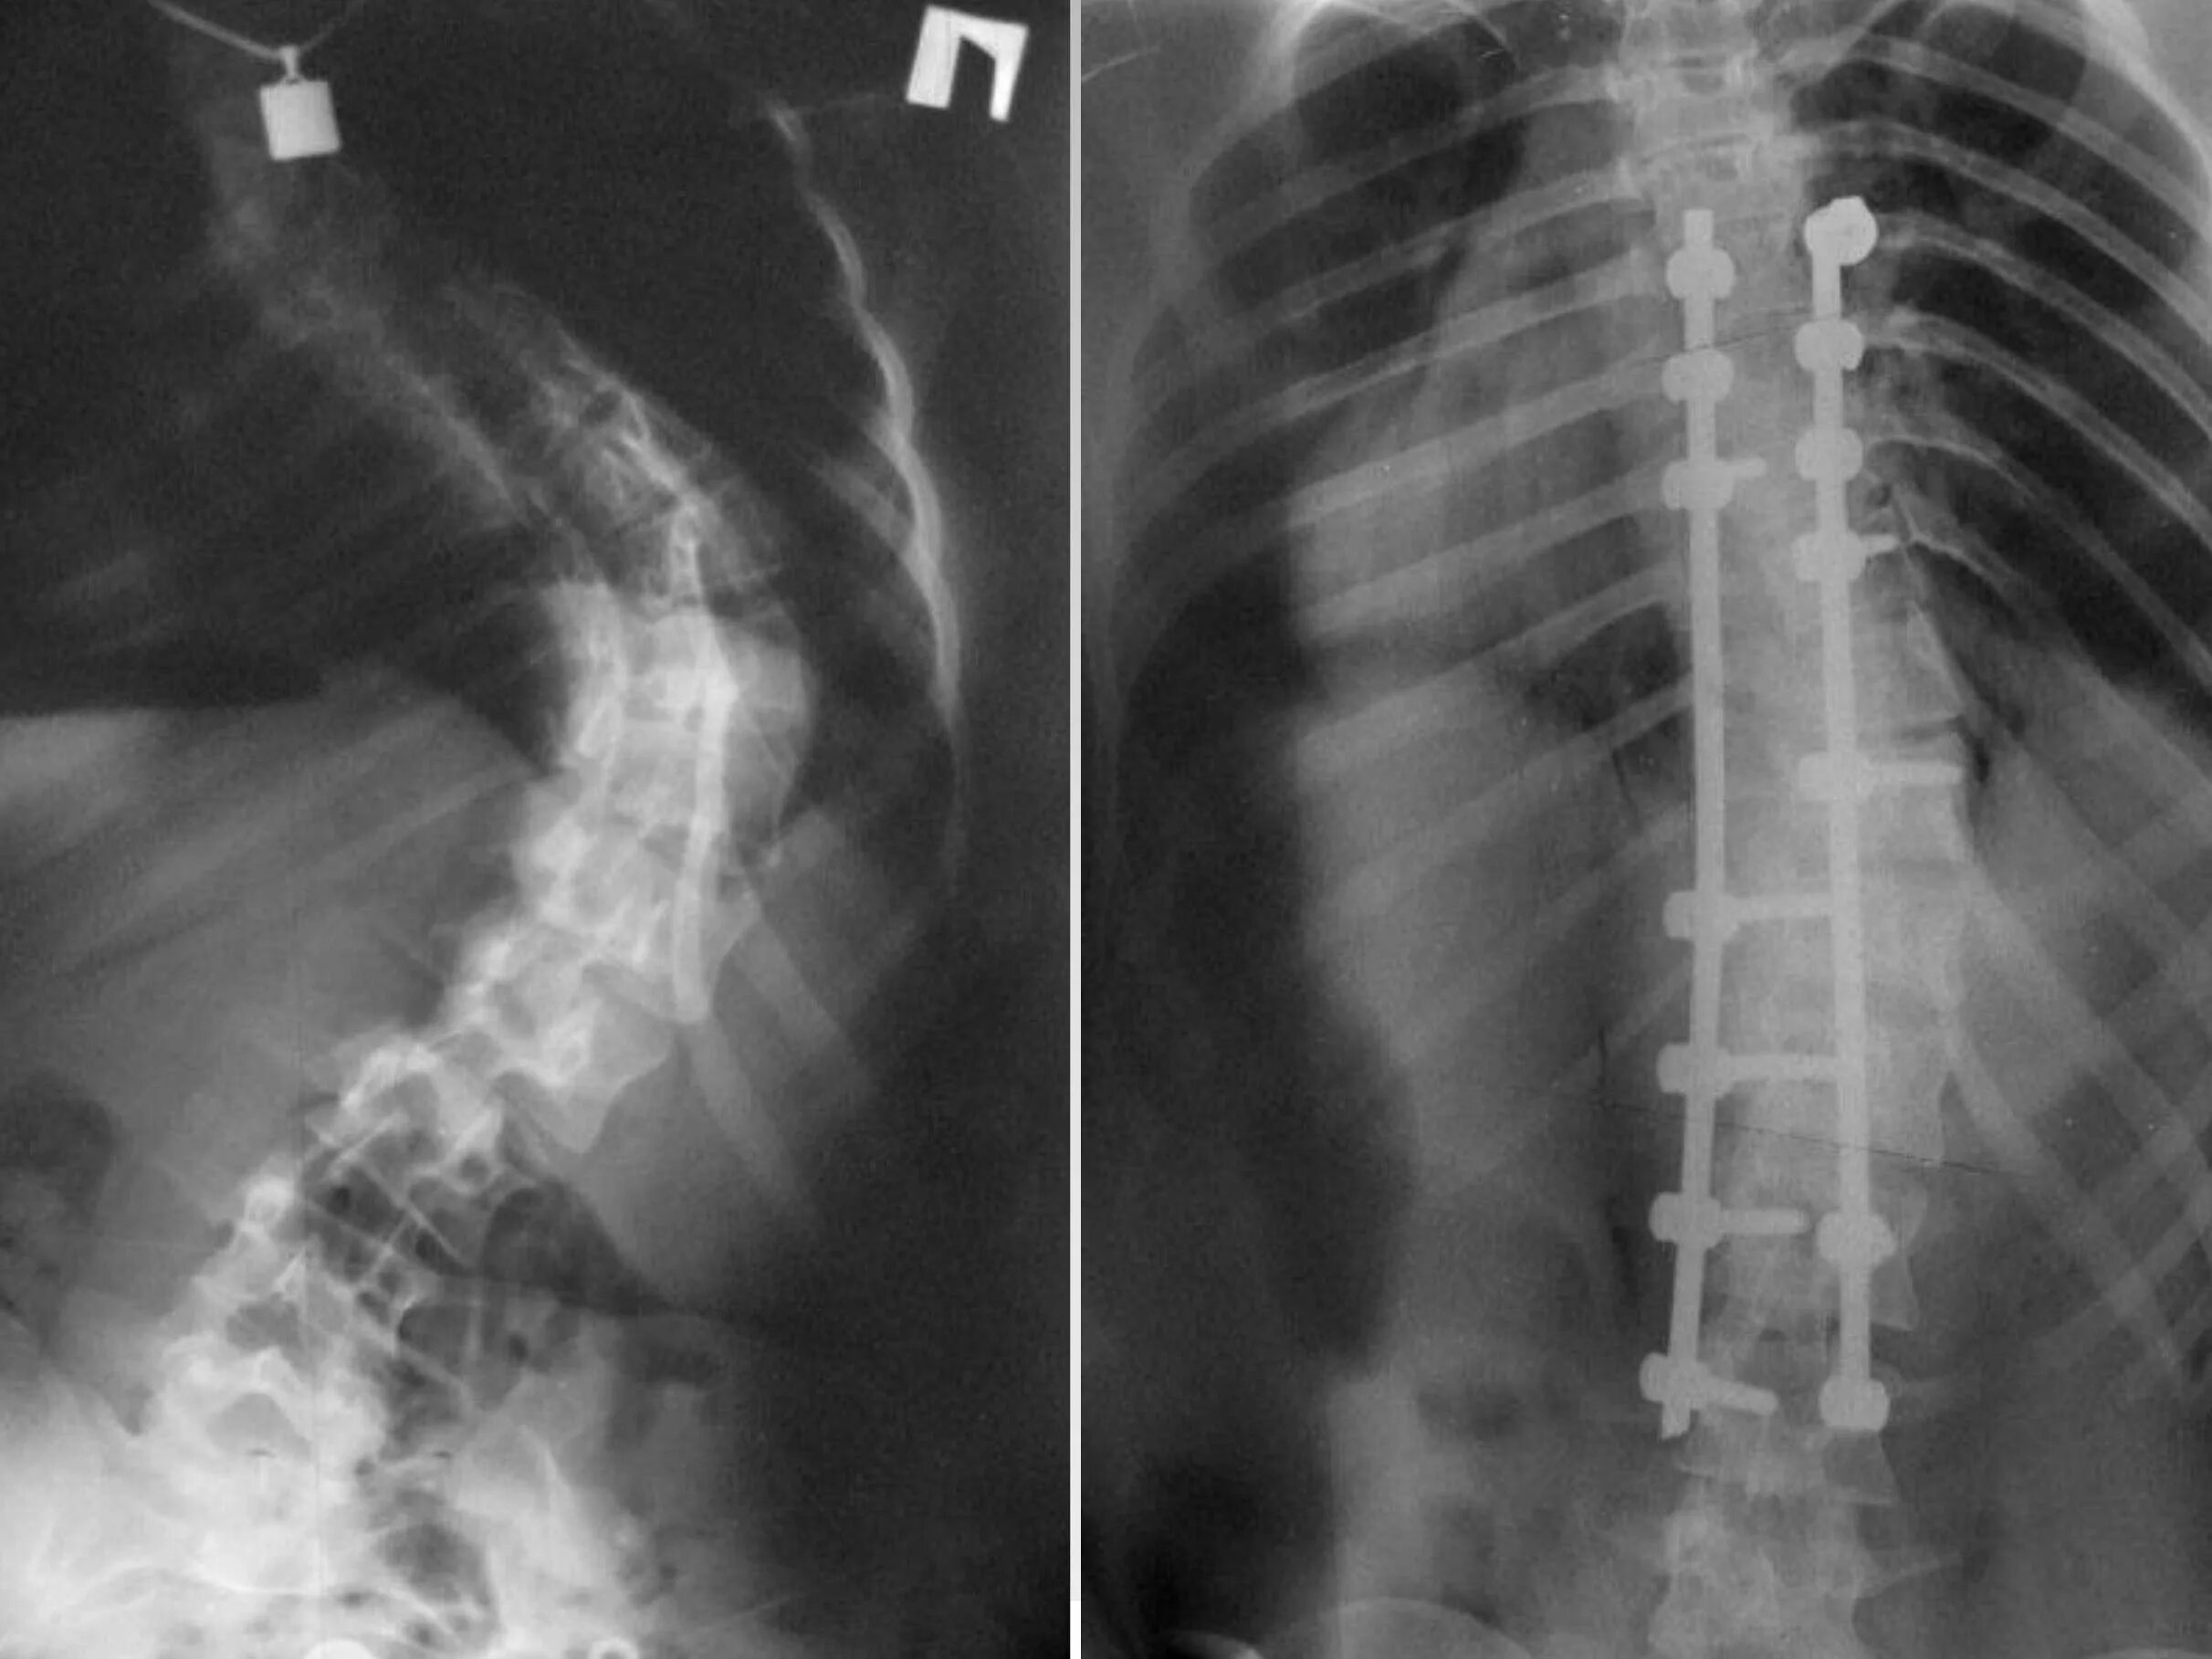

Сколиоз хирургия